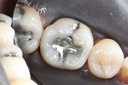

Larry Fujioka #20 amalgam removal